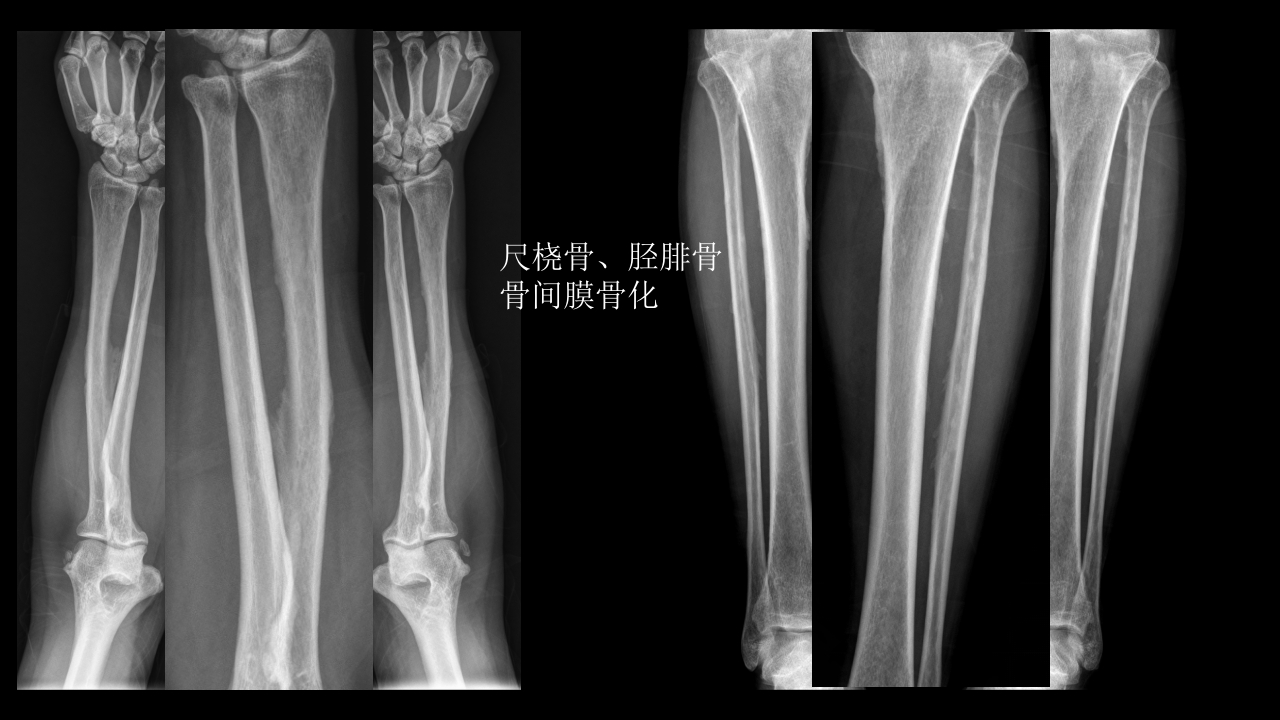

氟骨症的X线CT及MR影像及解读